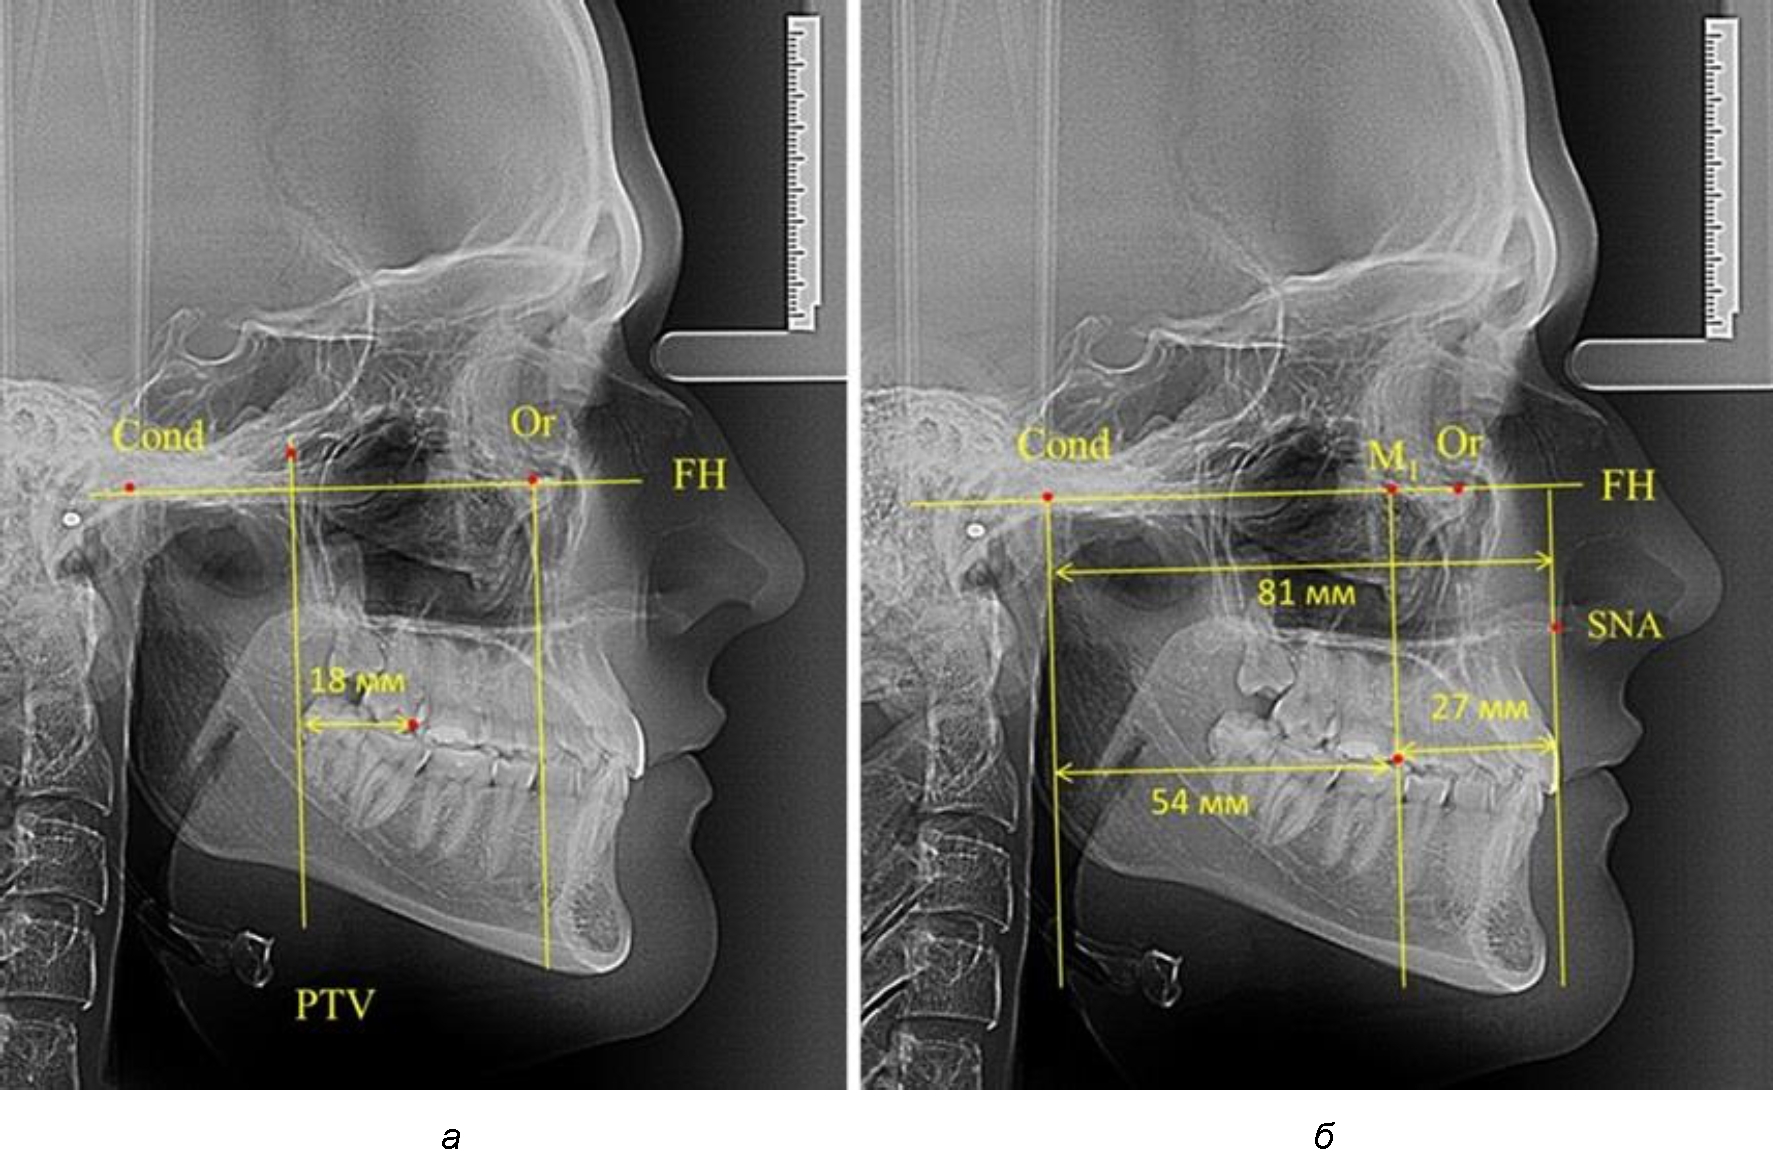

При проведении анализа к Франкфуртской горизонтали проводили передний и задний перпендикуляры. Передний спинальный перпендикуляр проходил через выступающую точку передней носовой ости (spina nasalis anterior – SNA), а задний суставной перпендикуляр опускали из кондилярной точки Cond. Молярный перпендикуляр проводили через медиальную поверхность первого постоянного моляра. Указанная вертикаль отделяла замещающие зубы постоянного прикуса от добавочных зубов (постоянных моляров), что вполне логично для анализа положения первых постоянных моляров в гнатическом комплексе (рис. 1).

Рис. 1. Метод определения положения первых верхних моляров по Ralph E. McDonald (а) и по предложенному методу (б)